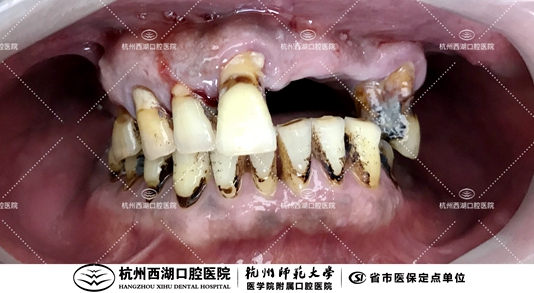

检查:慢性牙周炎

医生建议:提前拔除上颌部分牙齿,上颌即刻all-on-6

术前口内照片如下